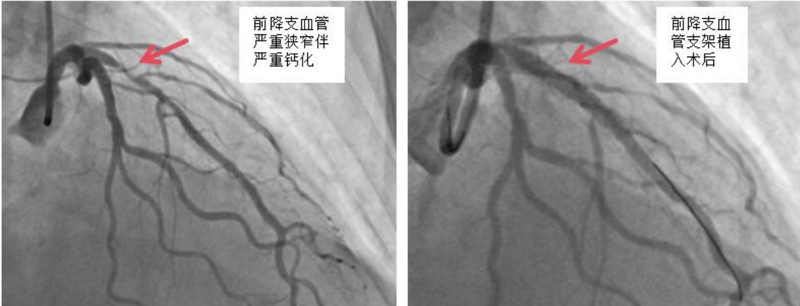

近日,中山大学附属第一医院(简称中山一院)广西医院心血管内科冠脉介入手术团队运用DEEPQUAKE-C冠脉血管内冲击波系统,顺利为一名冠脉严重钙化病变的冠心病患者开通堵塞的血管并完成支架植入,完成了DEEPQUAKE-C上市后全国首批、广西首例临床应用。

经过充分的术前评估和准备,我院心血管内科冠脉介入团队使用国产新器械DEEPQUAKE-C冠脉血管内冲击波系统为杨阿姨处理了前降支近段的严重狭窄钙化病变,随后又在血管内超声指导下精准植入冠脉支架,帮助杨阿姨顺利开通了堵塞的血管。术后杨阿姨恢复状况良好,目前已康复出院。